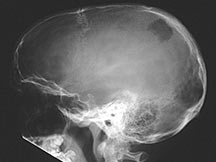

- Any bone but 90% have skull involvement

Sites:

- Flat Bones (most common—70%)

- Skull